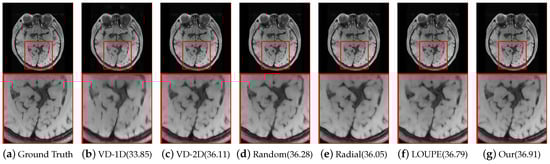

Figure 4 shows a visual comparison between the classical mask and our trained optimized sub-sampling ratio for | | S | | 0 = 10 % and | | S | | 0 = 20 % . It can be seen that the learned 2 D mask exhibits a strong preference for lower frequencies and a denser sampling pattern closer to the origin of K-space, which is also in line with prior knowledge, i.e., the lower frequency part has greater energy.

Table 1 lists the specific PSNR values when the CS ratio is set to 5%. As can readily be observed, the highest PSNR results can be obtained through the use of the proposed Samp-Net, which benefits from the efficient probabilistic under-sampling scheme. Taking the 5 % ratio of reconstructing the sub-network as an example, our Samp-Net achieves a significant 0.98 dB PSNR gain over the probability-based learnable mask LOUPE. This is because our learnable mask learns the point with the greatest weight of the fixed sample rate, and, as can also be seen from Figure 4, our learnable mask has a clearer structure and better represents the data structure of the dataset. It is also worth noting that U-Net still performs worse than our unfolding net when equipped with our Samp-Net, which indicates that deep unfolding networks incorporating prior knowledge are more suitable for promoting exploration and efficient training of our Samp-Net than classical data-driven reconstruction models. Figure 5 further shows a comparison of visual reconstructions under the reconstructed subnet when the CS ratio is set to 10%. From the comparison images, it is intuitive to see that the sampling mask learned using our proposed approach is able to consistently restore more detail and sharper edges than the other masks in the comparison.

Figure 4. Visual comparison of different masks on the Brain dataset. The CS ratios are set to 10% and 20%. Our learnable masks have a clearer data structure than other masks, and also satisfy the priors of low frequency density and high frequency sparseness.

Figure 5. Visual reconstruction comparison of different masks on the Brain dataset with a CS ratio of 10%.The PSNR values of the reconstructed results are also listed. Our proposed model can recover more detail and sharper edges.